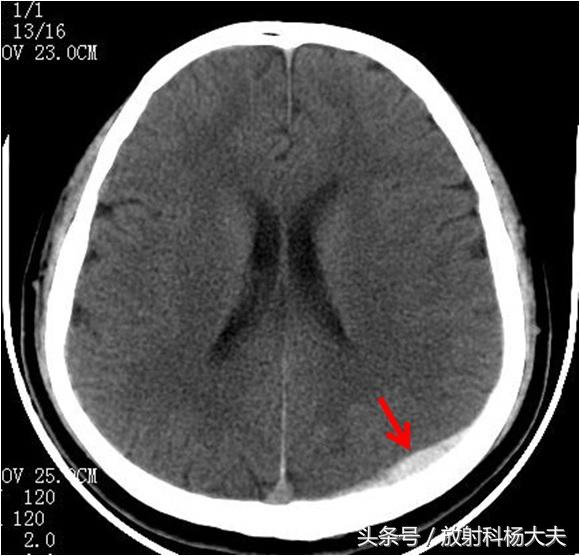

依据血肿形成时间, 将颅内血肿分为急性颅内血肿和迟发性外伤性颅内血肿。迟发性外伤性颅内血肿是指颅脑损伤后首次头颅CT检查未发现颅内血肿,复查头颅CT检查发现出现颅内血肿;或首次头颅CT检查发现颅内血肿, 复查头颅CT检查发现颅内其他部位又出现颅内血肿,或在清除颅内血肿后又于颅内其他部位出现血肿,或原有出血部位出血较前增多,是颅脑损伤常见继发性损害。迟发性血肿以硬膜外血肿较常见,其次为硬膜下。其中男性较为常见。多数患者有意识障碍或清醒后再次转入昏迷。迟发性血肿以额颞部较为常见。迟发性血肿的三个重要症状是入院时一般症状较轻、意识障碍进行性加重、逐渐出现局限性神经症状。

CT扫描是诊断外伤性血肿的主要手段。对于易发生迟发性颅内血肿的脑挫裂伤和外伤性蛛网膜下腔出血的高危患者最好能在重症监护病房进行生命体征的监测,并常规于住院后内行头颅复查以便及早发现并治疗迟发性血肿。对于那些外伤后活蹦乱跳的患者,特别是特别兴奋的患者,尤其要提高警惕,预防迟发性外伤性出血的可能。记住,有一种爱叫迟来的爱,有一种出血叫迟发性出血。